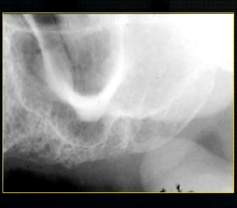

oblique lateral technique allows you to take extraoral radiographs

image receptor is placed outside the mouth and against the side of the face

resultant radiographs are larger and show anatomical structures in both jaws

direction of Xray beam on this skull

for right hand side - tube head left and receptor opposite - passes between the cervical spine and the left ascending ramus of the mandible - viewed like you are looking at the patient’s right cheek

posterior edge of left side

radiolucent band around the posterior part of the body of the mandible

created by inferior dental nerve and blood vessel, created by the inferior dental canal

the edges of the canal can be seen as thin, white radiopaque lines → ‘tram lines’